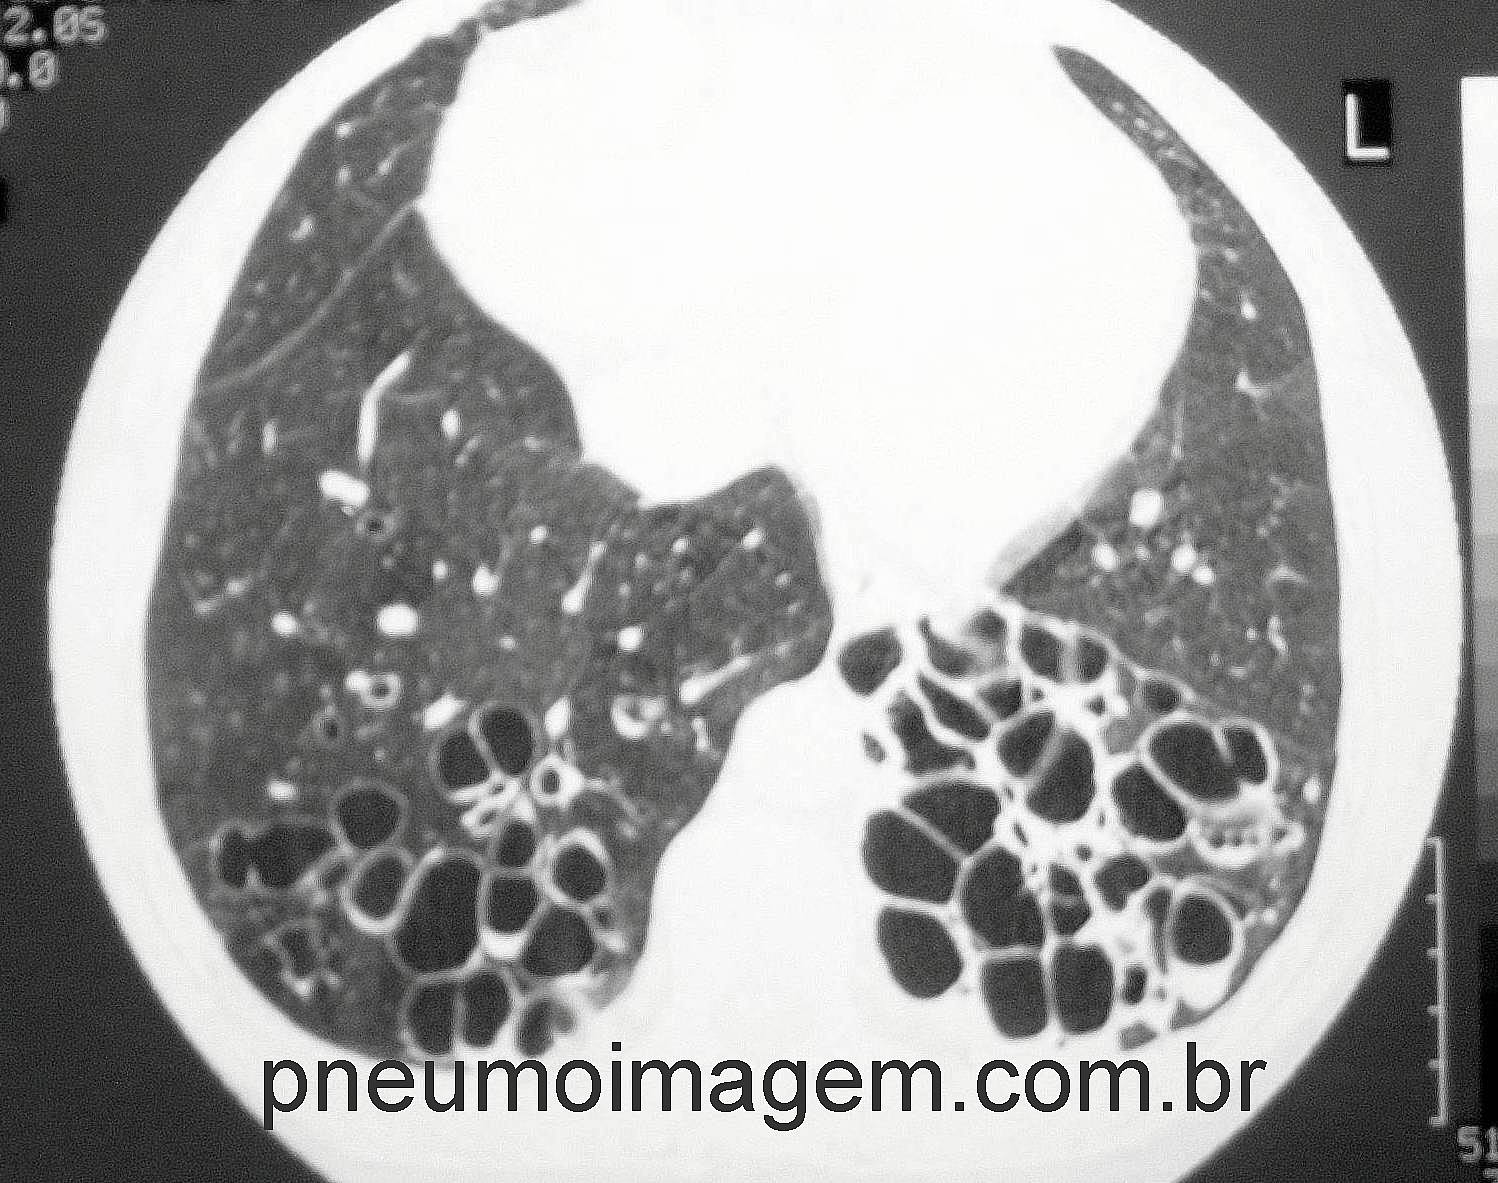

• Frequência de exacerbações em bronquiectasias

Clique aqui para ler mais sobre a colonização pulmonar e o tratamento em bronquiectasias no PneumoImagem.